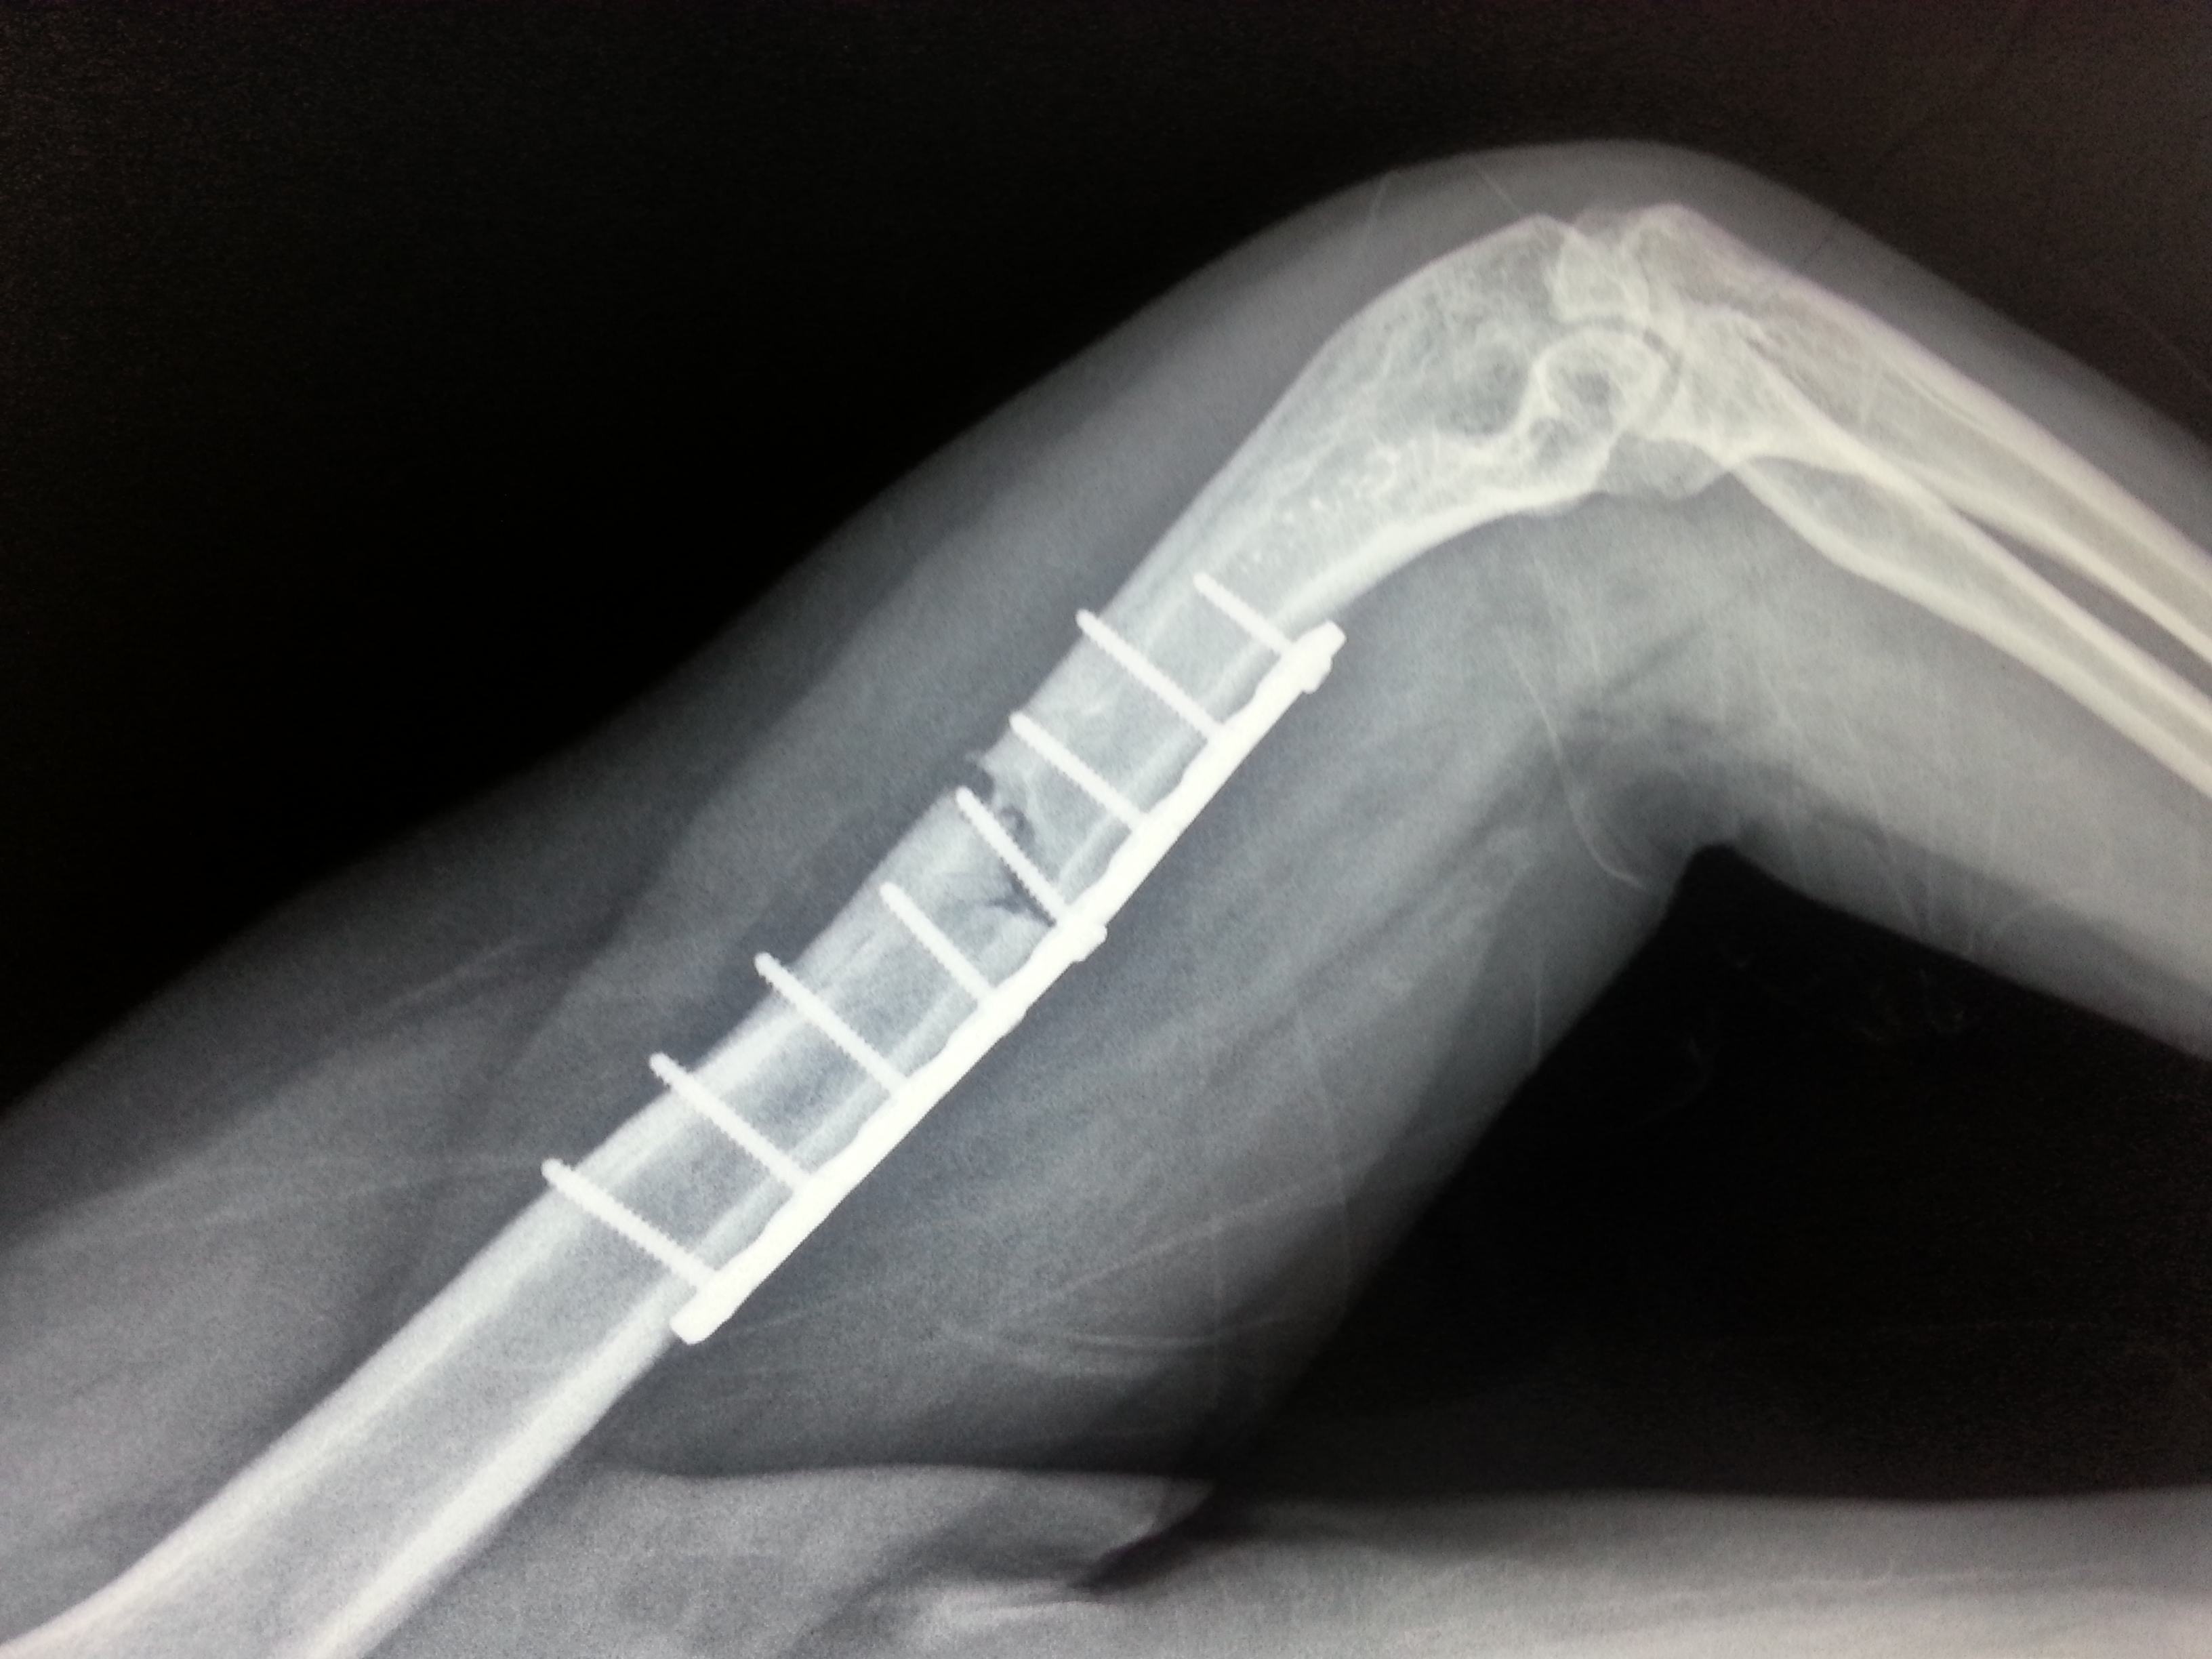

胫骨骨折术后钢板断裂

胫腓骨9个月复查钢板断了.

黄骨头胫腓骨骨折初次术后半年钢板断裂假关节形成一例